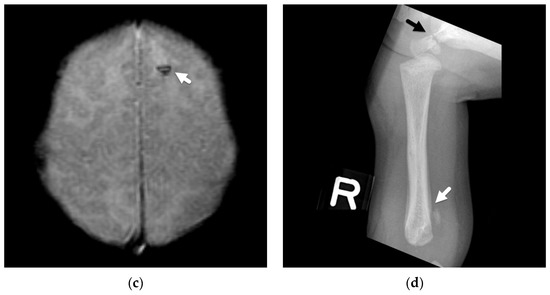

4. Focal Parenchymal Insults

5. Imaging Evaluation